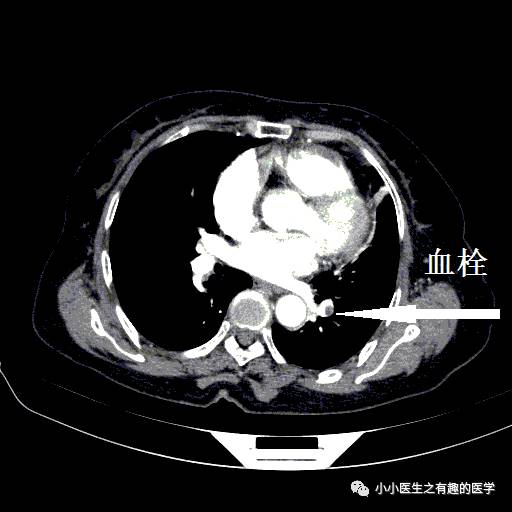

左侧血栓,对比右侧就很通畅,一路顺风。

这条公路,全程阻塞,后方车辆请绕行。